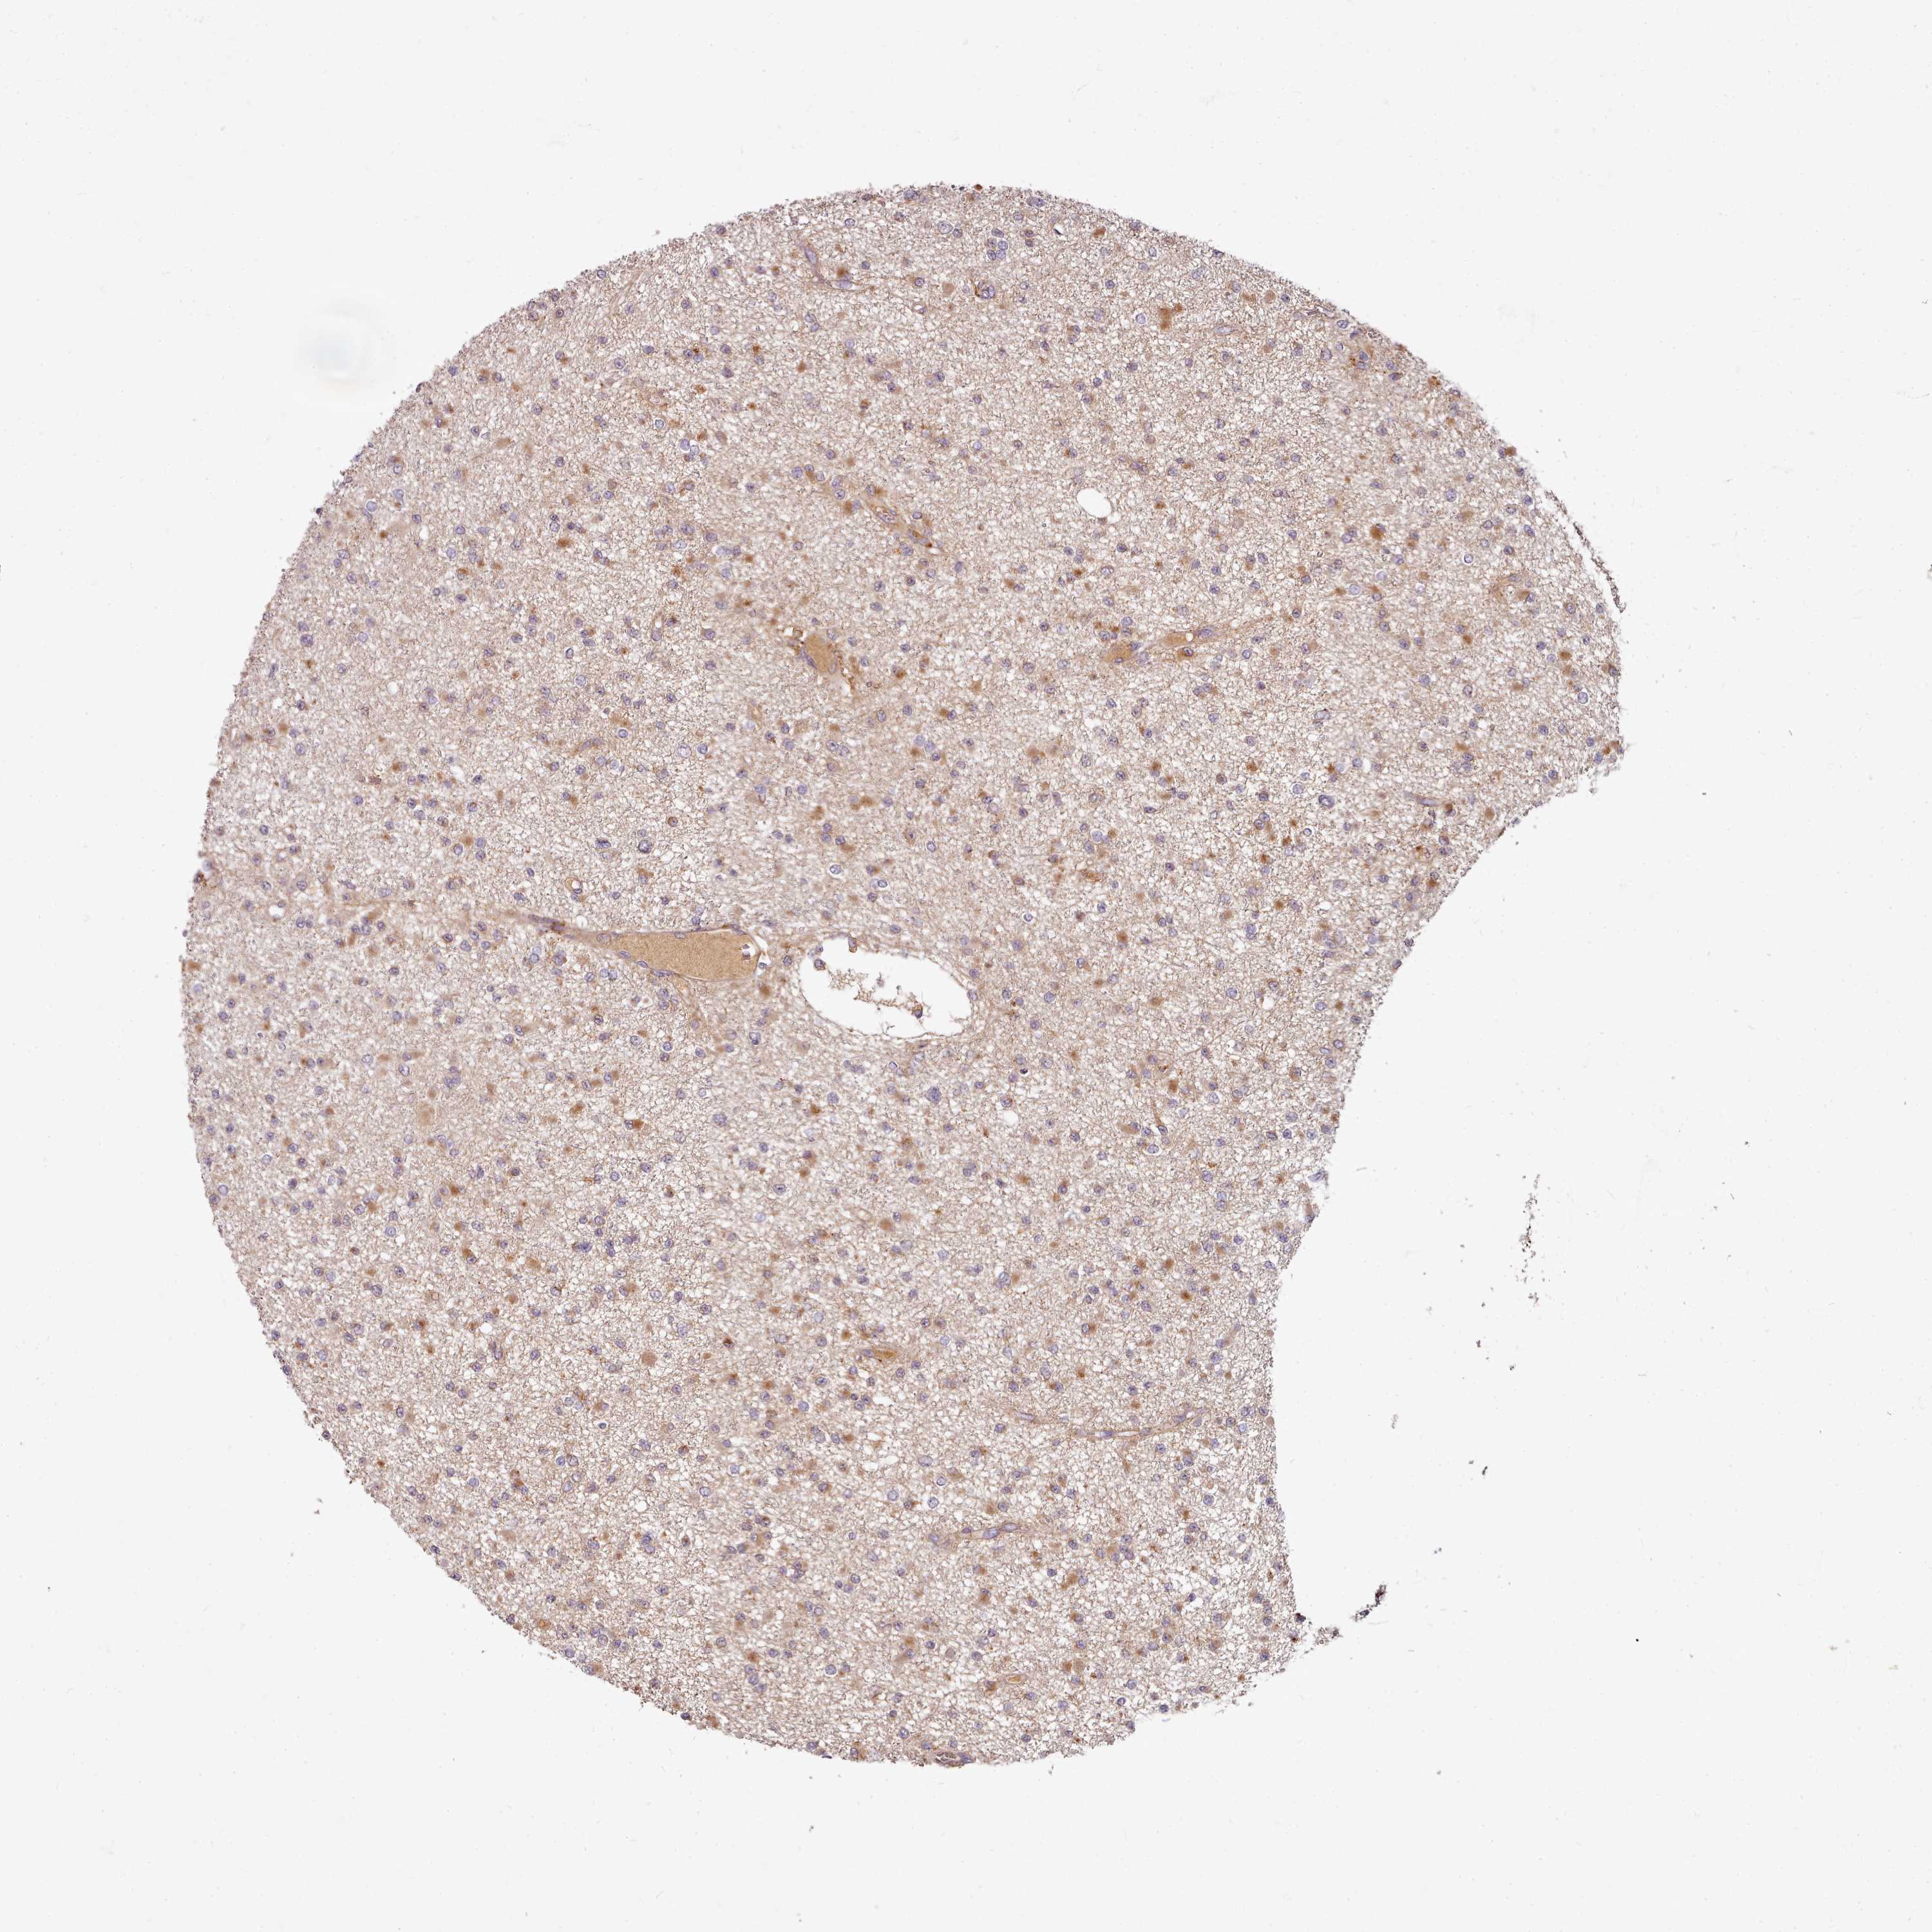

GLIOMA - Protein expressioni

A mouse-over function shows sample information and annotation data. Click on an image to view it in a full screen mode. Samples can be filtered based on level of antibody staining by selecting one or several of the following categories: high, medium, low and not detected. The assay and annotation is described here.

Note that samples used for immunohistochemistry by the Human Protein Atlas do not correspond to samples in the TCGA dataset.

Antibody stainingi

Antibody staining in the annotated cell types in the current human tissue is reported as not detected, low, medium, or high, based on conventional immunohistochemistry profiling in selected tissues. This score is based on the combination of the staining intensity and fraction of stained cells.

Each image is clickable and will lead to virtual microscopy that enables deeper exploration of all samples and also displays staining intensity scores, fraction scores and subcellular localization as well as patient and tissue information for each sample.

Antibody HPA038604

Antibody CAB025607

Staining

High

Medium

Low

Not detected

Intensity

Strong

Moderate

Weak

Negative

Quantity

>75%

75%-25%

<25%

None

Location

Nuclear

Cytoplasmic/membranous

Cytoplasmic/membranous,nuclear

Glioma, malignant, High grade

Glioma, malignant, Low grade